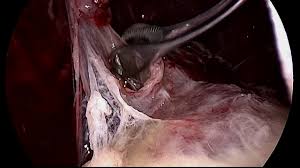

Role Of Medical Thoracoscopy In The Management Of Multiloculated Empyema Springerlink

Role Of Medical Thoracoscopy In The Management Of Multiloculated Empyema Springerlink from media.springernature.com